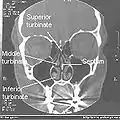

تصوير طبقي محوري لأنف طبيعي

حاجز الأنف.